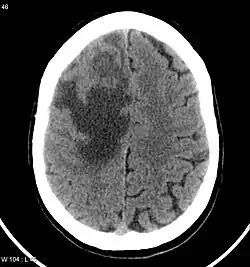

CNS metastases are diagnosed through imaging techniques that produce detailed images of the inside of the body, including parts such as the bones, organs, muscles, and nerves.[13] Magnetic resonance imaging (MRI) and computed tomography (CT) are two representative imaging procedures for this purpose.[12]

MRI scans use strong magnetic fields and radio waves to create an image, while CT scans use X-rays. MRI scans produce more detailed images of bodily structures, particularly soft tissues including the brain,[13] and are better at detecting CNS metastases than CT scans. However, CT scans are sometimes used for the initial imaging modality due to their lower cost and efficiency in screening for multiple conditions.[14]